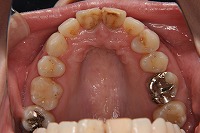

上顎

前歯が出ていて歯並びが悪い事を主訴に来院された、26歳1か月の女性です。診断「歯と歯槽基底の大きさの不調和による叢生」上顎は右側第1小臼歯と左側の犬歯、下顎は抜歯をせず治療を行いました。